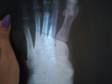

Подскажите или есть перелом на снимке??

Подскажите или есть перелом на снимке 5 плюсневой кости стопы?? 26 лет. Девушка. 3 недели ходила с шиной, сняли, сделали снимок, врач ничего не сказал. Сказал придти через неделю. Можно ли наступать на эту ногу(хотя бы на пятку).